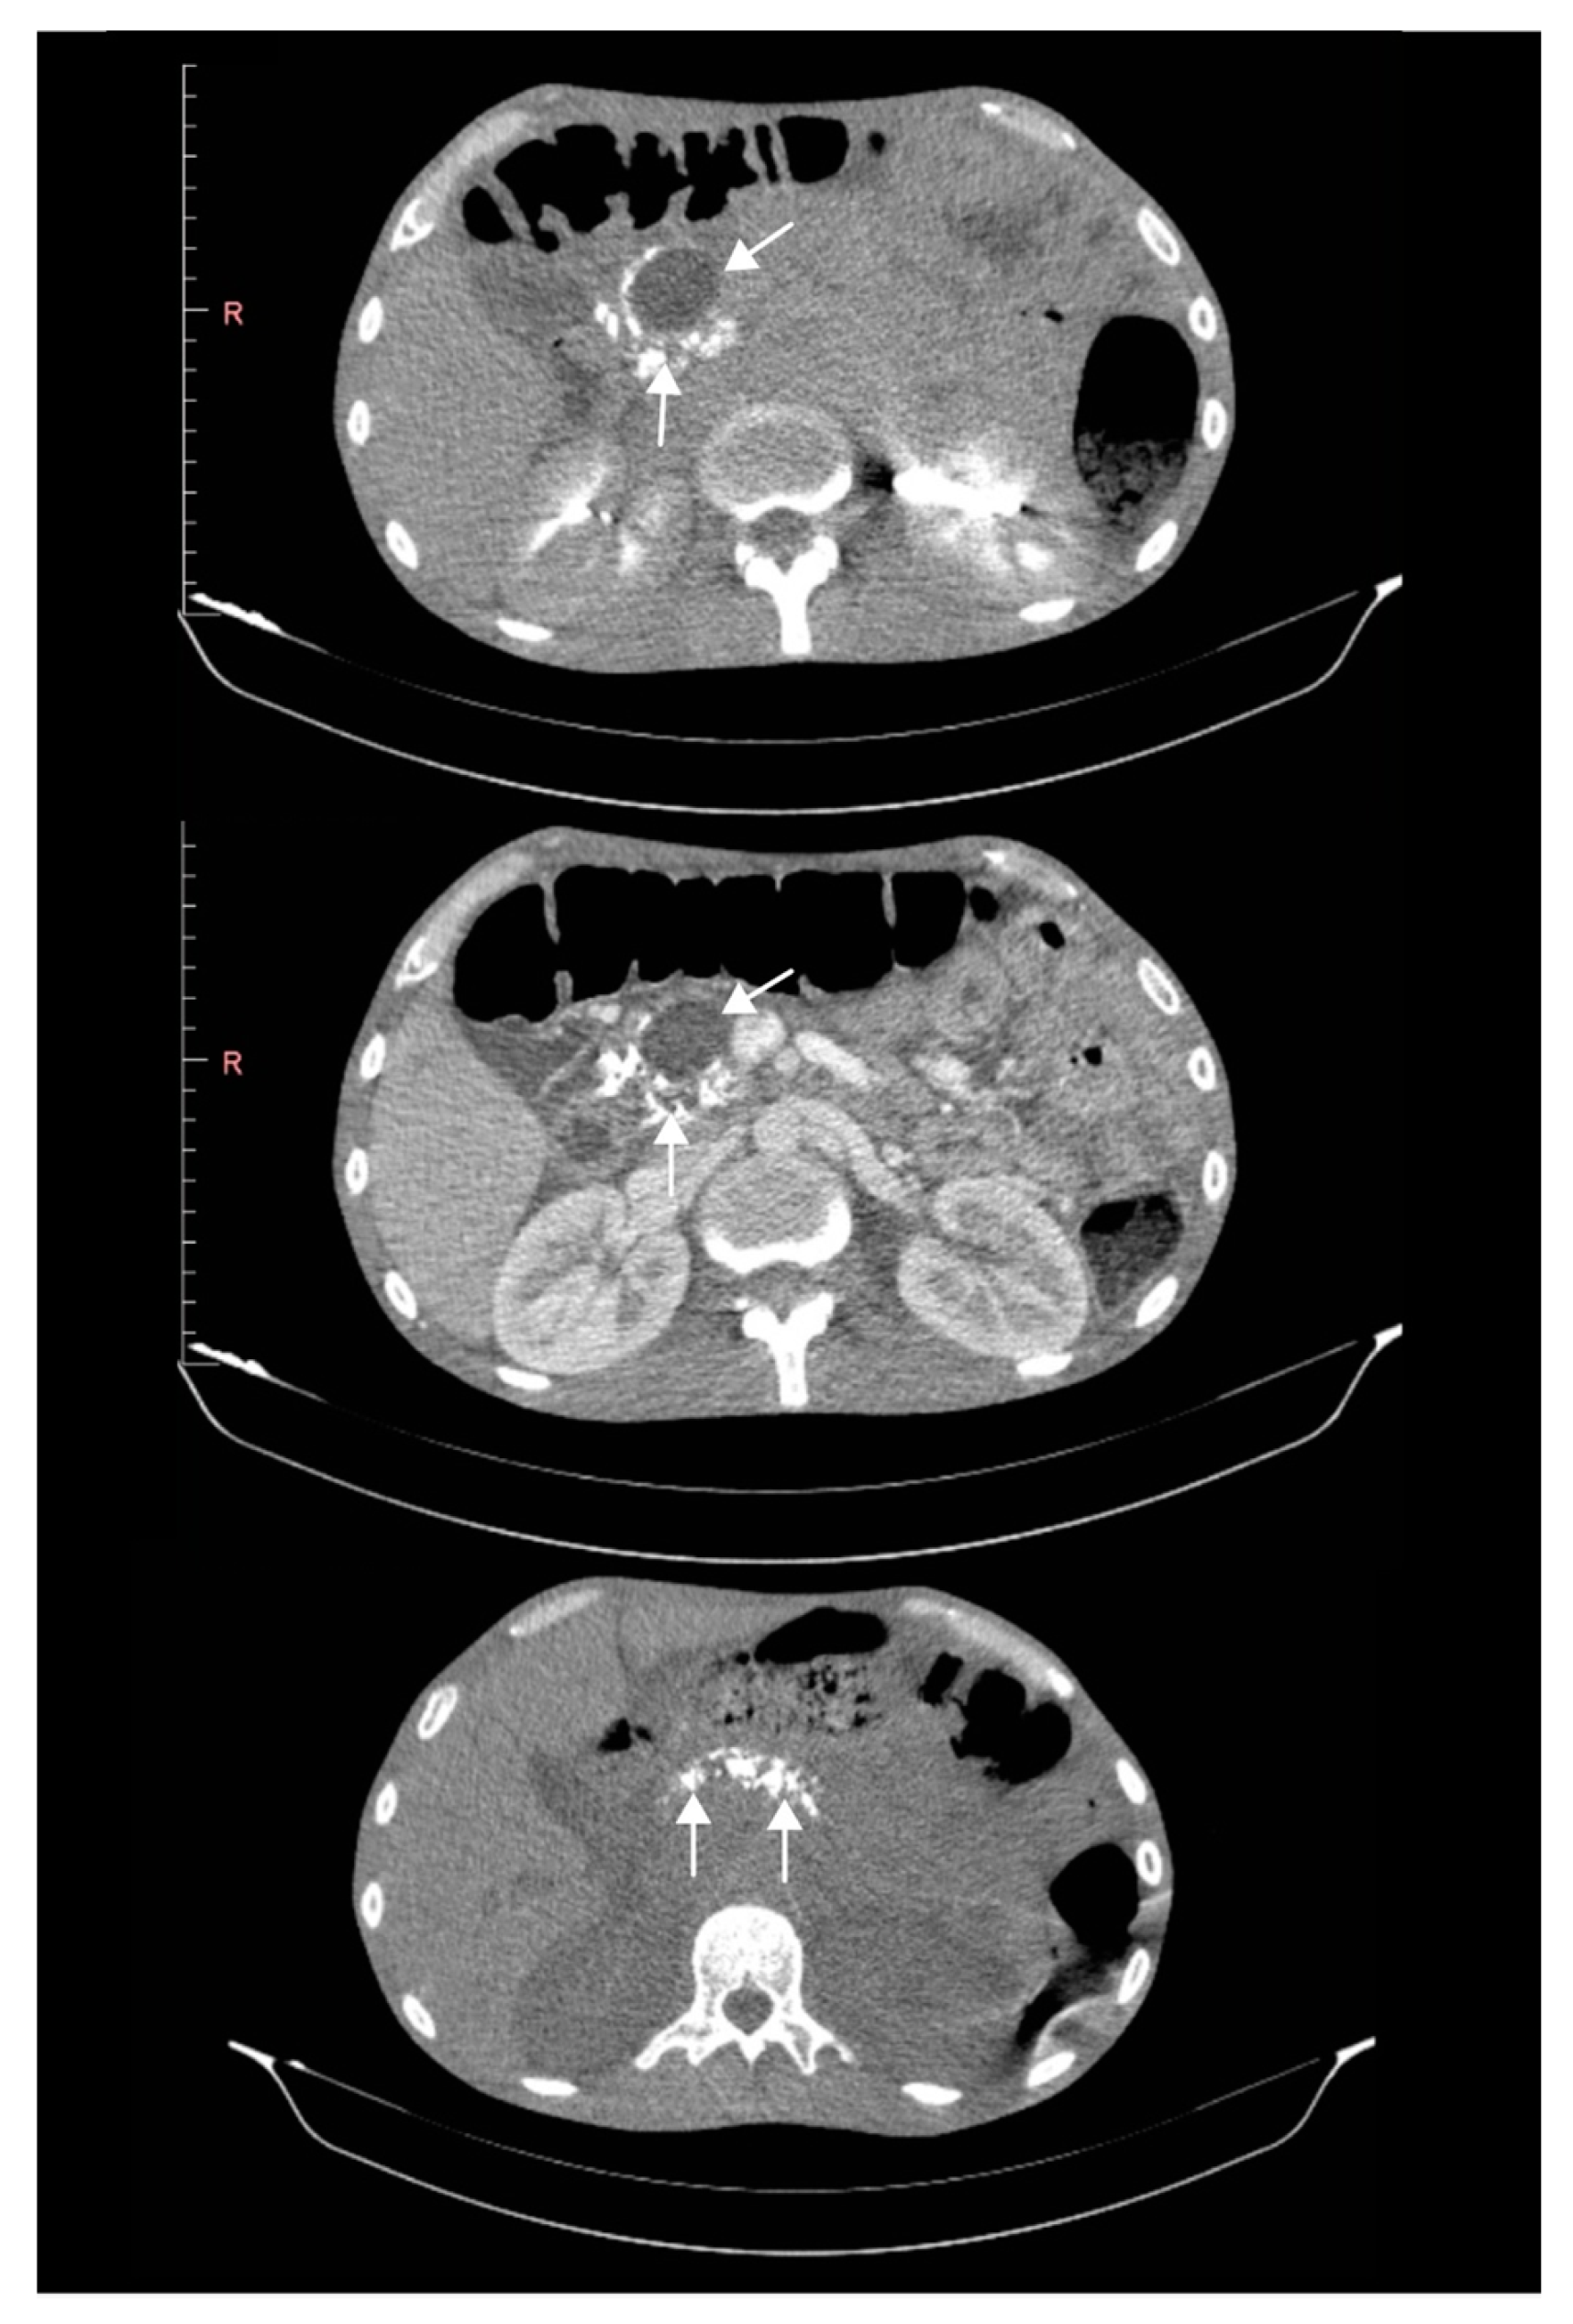

Chronic Calcifying Pancreatitis Associated with Secondary Diabetes Mellitus and Hepatosplenic Abscesses in a Young Male Patient: A Case Report

2. Case Report